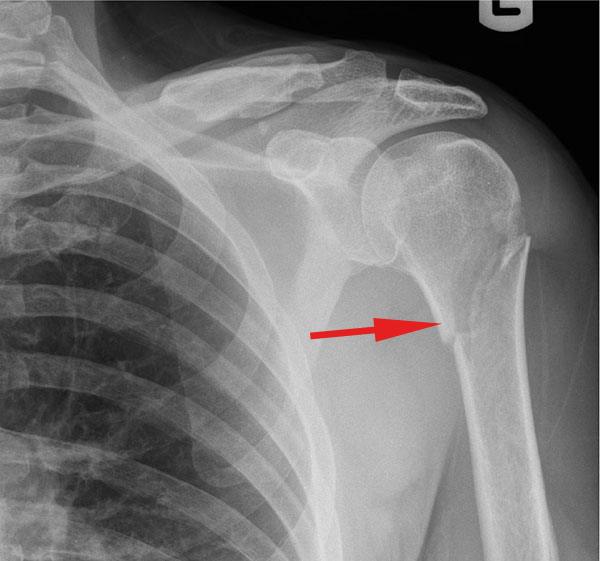

.2تصویربرداری